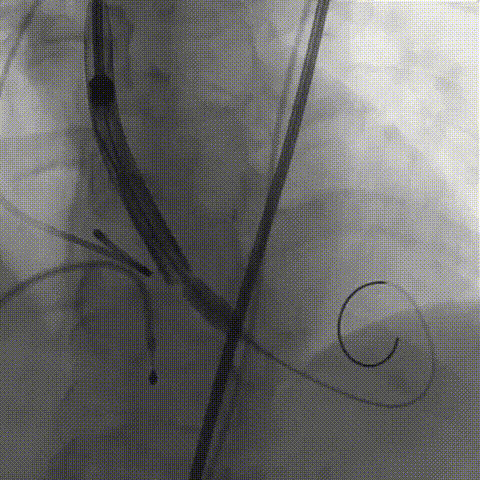

瓣膜膨胀不良

瓣膜膨胀不良进行球囊后扩

球囊后扩后造影无漏